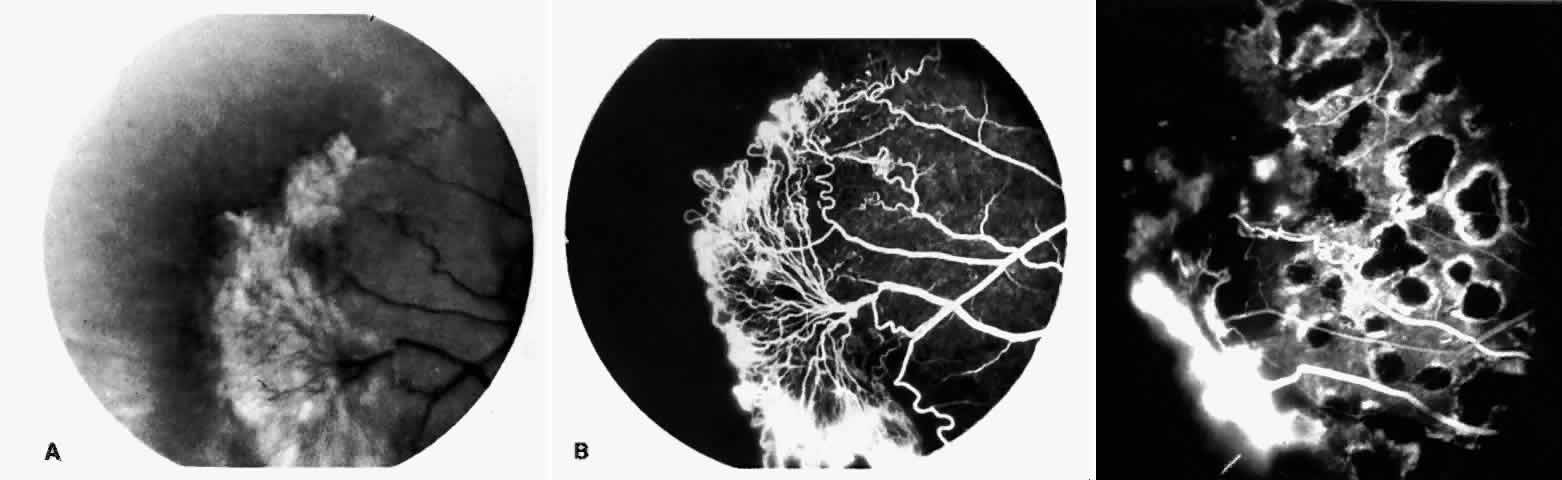

STAGE III: PRERETINAL NEOVASCULARIZATION (PROLIFERATIVE SICKLE RETINOPATHY). “Sea fan”-shaped neovascularization typically develops on the venular side of an arteriolar-venular anastomosis, mimicking the normal development of retinal capillaries (Fig. 24).125 A lowered oxygen tension and angiogenic factors released on the venular side may be the stimulus for neovascular growth.125,126 In most instances, the direction of growth is toward the ora serrata, from the perfused retina toward the nonperfused retina. Presumably, this represents an abortive attempt to revascularize the nonperfused retina, initiated by vasoproliferative factors.

Fig. 24. A. Photograph of the peripheral retina, demonstrating several small fibroglial membranes. B. Fluorescein angiogram corresponding to A, showing multiple arteriolar-venular anastomoses with early sea fan formation. C. Photograph of the same area 2 years later demonstrates more fibroglial membranes. D. Fluorescein angiogram corresponding to C shows new sea fans caused by an arteriolar-venular anastomosis (curved arrow). Large arrow (A through D) identifies corresponding arteriolar bifurcation.

The characteristic neovascular lesions of PSR are called sea fans because they resemble the marine invertebrate Gorgonia flabellum.70 They tend to occur more commonly in the temporal periphery, but they have been reported to occur in the temporal macula in the presence of extensive nonperfusion.130,133 Initially they grow on the surface of the retina, but they often become elevated into the vitreous and adhere to a partially detached posterior hyaloid.114 It may be difficult to visualize small sea fans ophthalmoscopically; however, fluorescein angiography clearly demonstrates leakage of dye into the vitreous (Fig. 25). The feeding arteriole is usually more tortuous than the draining venule (Fig. 26). Early on, the neovascular lesion is fed by a single arteriole and drained by a single venule, but with time, additional arterioles and venules become arborized within the lesion (Fig. 27).129 Growth of the sea fan often occurs circumferentially, rather than radiallyÜmh- 1Ý, toward the ora serrata. Progressive circumferential growth may lead to neovascular lesions extending around the entire periphery. As it matures, a white fibroglial mantle often covers the neovascular tissue (Color Plate 2B).